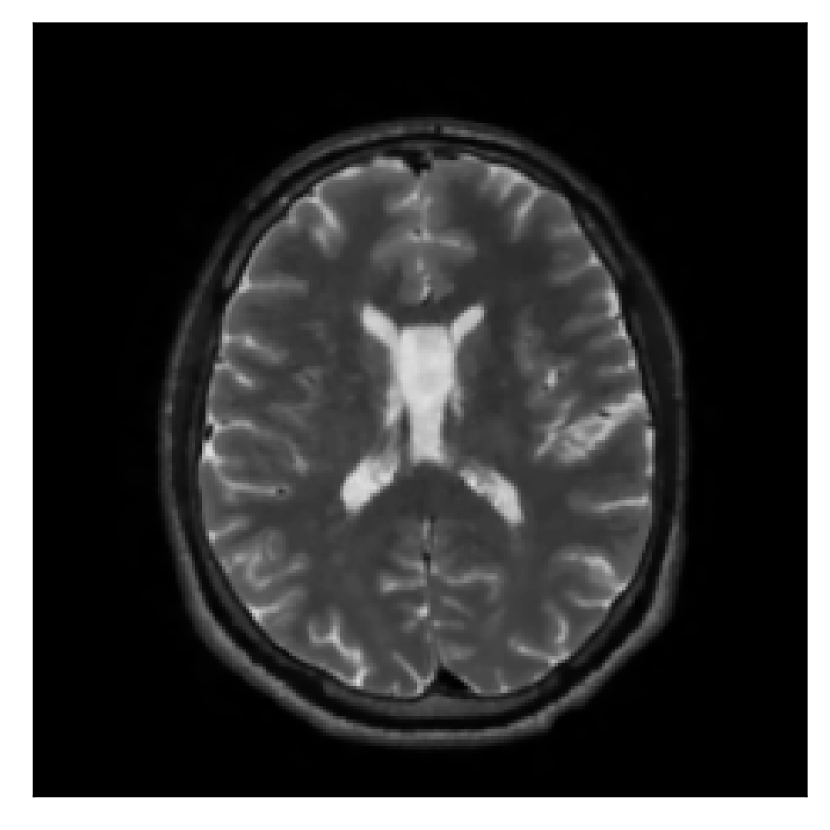

3.3 Experiment 3: scanner reconstruction vs processed raw k-space data as input for retrospective motion correction

With the in-vivo studies presented in this section, we investigate a question related to the nature of the input data (equation 6) required by the algorithm. Due to the formulation of the problem directly in -space (by means of the NUFFT), the method assumes coil-resolved data. One must then assess whether the scanner reconstruction (available in the DICOM format) is suitable for this purpose, since many different reconstruction methods are available depending on the acquisition protocol. In particular, the default reconstruction method for linear-filling patterns in -space employs the SENSE framework [Pruessmann et al., 1999], while compressed-sensing reconstruction (via the wavelet transform) is used for randomized acquisitions [Lustig et al., 2007]. Note that our experimentation suggests that without the phase map of the scanner reconstruction our motion correction scheme does not perform adequately. Therefore, with “scanner reconstruction”, we will always refer to the complex-valued scanner reconstruction (comprising both the respective amplitude and phase).

The second experiment is set up similarly to the previous one. We asked volunteer 3 to change position only once during the acquisition phase. We consider, now, a corrupted T2-FLAIR-weighted contrast with a reference T1-weighted contrast (see Table 1). The most important difference with the previous experiment, besides the type of contrast pair considered, is related to the randomized acquisition protocol. In this case, the scanner reconstruction employs a compressed-sensing reconstruction, and is not suited as input for the proposed motion-correction algorithm (see Appendix A). Therefore, for adequate motion correction, we must set up an intermediate step for processing the raw -space data via the SENSE reconstruction.

We further discuss the results of this experiment in Section 4.3.

| Section 3.3, Figure 14 | Sagittal | 24.72 | 28.76 | 0.6762 | 0.7818 |

| Coronal | 25.95 | 29.54 | 0.7238 | 0.8107 | |

| Axial | 25.08 | 29.59 | 0.7263 | 0.8407 | |

The motion-corrected full-volume scans were analyzed by a neuroradiologist with 16 years of experience. These were generally deemed of good radiological quality. The motion-related artifacts have been completely removed, and the results are quite close to the ground truth. In Table 3, we organized a more detailed qualitative analysis of the 3D results, geared toward a radiological assessment of the corrected scans.

| Section 3.3, Figure 14 | T2-FLAIR | Completely corrected | Some blurring | No additional artifacts | Good grey white matter differentiation |

4.3 Experiment 3: scanner reconstruction vs raw k-space data

The results of the two experiments described in Section 3.3 are depicted in Figures 12 and 14. The main difference between the two experiments is related to the input data for the proposed motion-correction algorithm.

In the case of randomized sampling, the scanner reconstruction is not adequate as input data for the proposed motion-correction algorithm, because it employs a compressed-sensing algorithm. We speculate that compressed-sensing reconstructions degrade the information contained in the corrupted volume, and the corrected contrast cannot be effectively recovered by simply removing rigid-motion artifacts (we defer the degraded results when using scanner reconstruction data in Appendix A). However, when the input data is obtained by directly processing the raw -space data via the SENSE reconstruction, the motion-correction scheme is able to successfully remove the motion artifacts (Figure 14).

A significant part of our experimentation was devoted to assess whether the scanner reconstruction (available as DICOM format) can be directly used as input data for the proposed correction method (Section 4.3). We established that the scanner reconstruction is not suitable for this purpose when it is obtained via compressed-sensing algorithms (Appendix A), which is the case for randomized sampling on the 1.5 T Philips Ingenia scanner utilized in this work. In this case, we must resort to the raw -space data and perform an intermediate SENSE reconstruction for effective motion correction.

Sagittal

Coronal

Axial

Axial detail